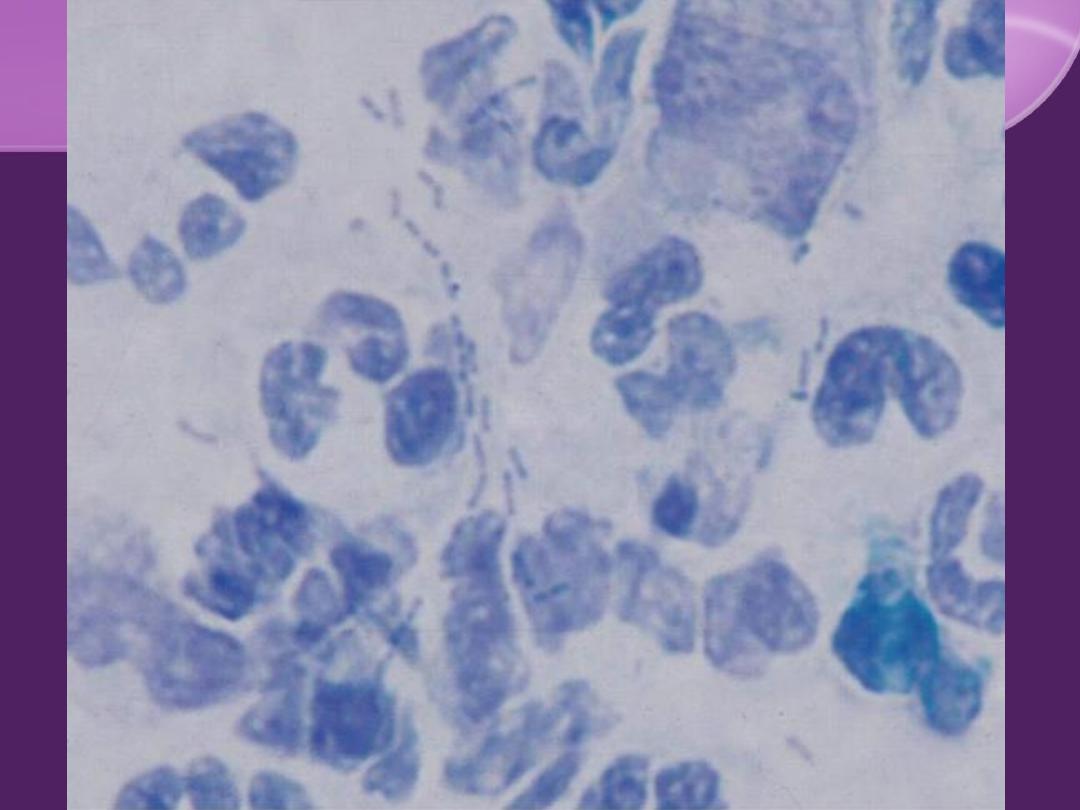

Investigation:

Smear: "school-of-fish" pattern.